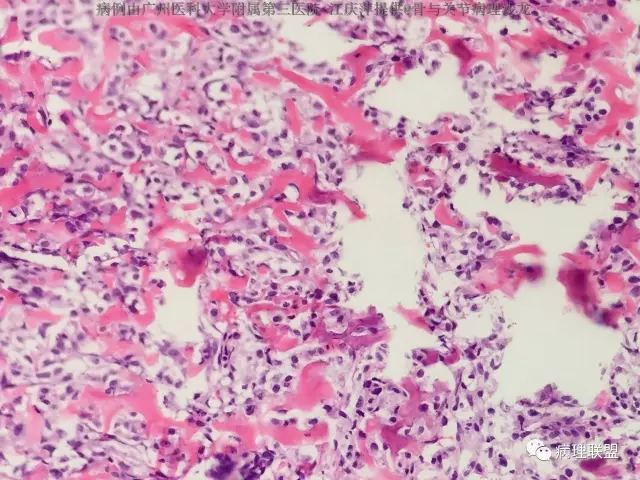

女,63,反复髋关节疼痛30年,活动受限2周(病例由广州医科大学附属第三医院 江庆萍提供,致谢)